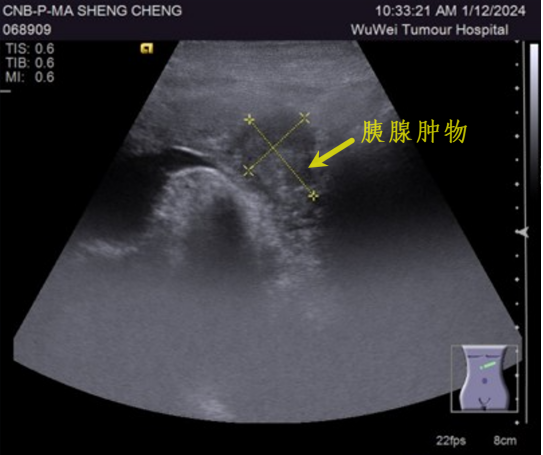

胰腺肿物穿刺活检

胰腺肿物 超声引导下穿刺活检